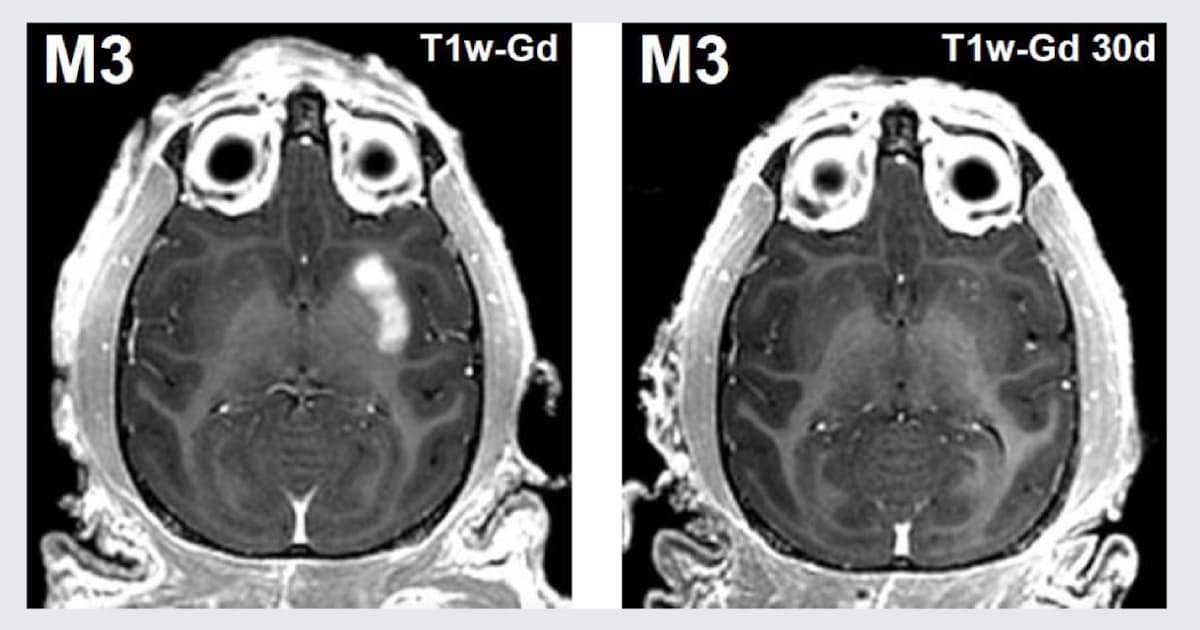

京都大学の高田昌彦特任教授と井上謙一助教は、

脳疾患を対象とした遺伝子治療で患者の負担を軽減する手法を新たに開発したと発表した。

超音波を活用することで脳の血管を一時的に広げ、

開頭することなく治療用の遺伝子を患部に届けることができる。

動物実験で確認したレベルだが、今後、パーキンソン病など神経疾患の治療法の開発につながるとみている。